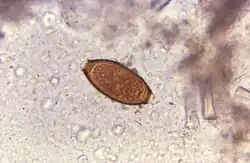

In an experimental idea called helminthic therapy, moderate hookworm infections have been demonstrated to have beneficial effects on hosts who have diseases linked to overactive immune systems. This may be explained by the hygiene hypothesis.[36] Hookworm therapy is currently in the trial stage at the University of Nottingham. Due to the unconventional nature of this therapy, it is not widely used.